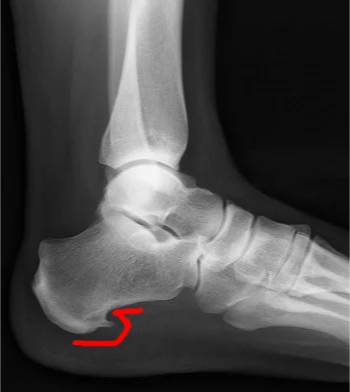

Radiology - Plantar Fasciitis

- “Calcaneal Spur” on XR:

- It’s a result NOT the cause

- Implies chronicity

- Not diagnostic

- Present in 10% of normal